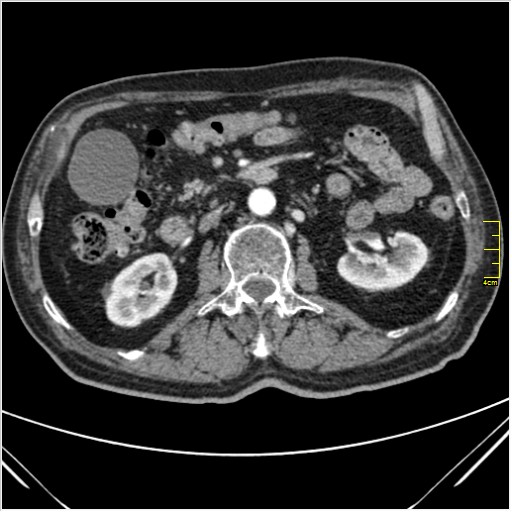

Мужчина 62 года с желтухой

Опухоль головки поджелудочной железы, расширение холедоха и панкреат. протока (Double Channel sign)

Карциномы панкреас гиподенсны на КТ с болюсом, т.к. содержать много соединительной и фиброзной ткани, в отличие от нормальной ткани железы, которая (как любая железа) хорошо васкуляризирована. Поэтому если видим в панкреас солидное гиподенсное образование - всегда настораживает на предмет рака. Второй момент: обязательная оценка взаимоотношения опухоли к ВБА и ВБВ, на предмет оценки операбельности.

pancr7.JPG

pancr7.JPG (62.38 КБ) 2898 просмотров